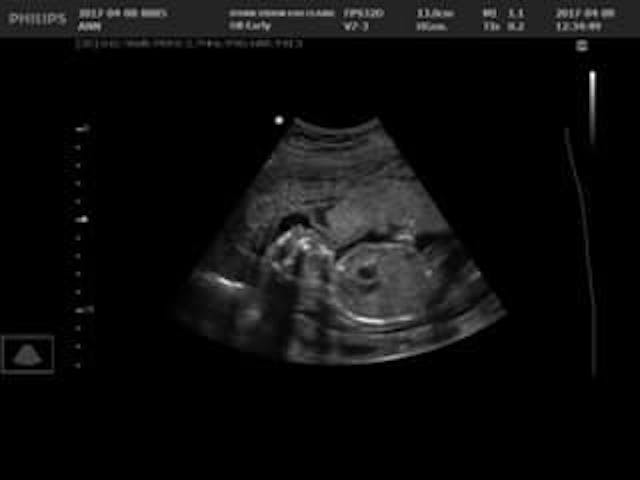

Already facing a high-risk pregnancy due to complete placenta previa, it was during a 14-week ultrasound that Ann Mahner first heard the word “anencephaly” used to describe her daughter. She had volunteered at the local pregnancy resource center two days earlier as a model for staff to practice on the new ultrasound machine. They could see that something wasn’t right, but without the doctor present, no diagnosis could be made.

Then, during the 20-week ultrasound, doctors found that the complete placenta previa had moved up and out of the way, which the Mahners call a complete miracle. The fear of rupturing and bleeding was gone; they wouldn’t have to deliver via C-section, and Miriam could arrive on her own schedule.